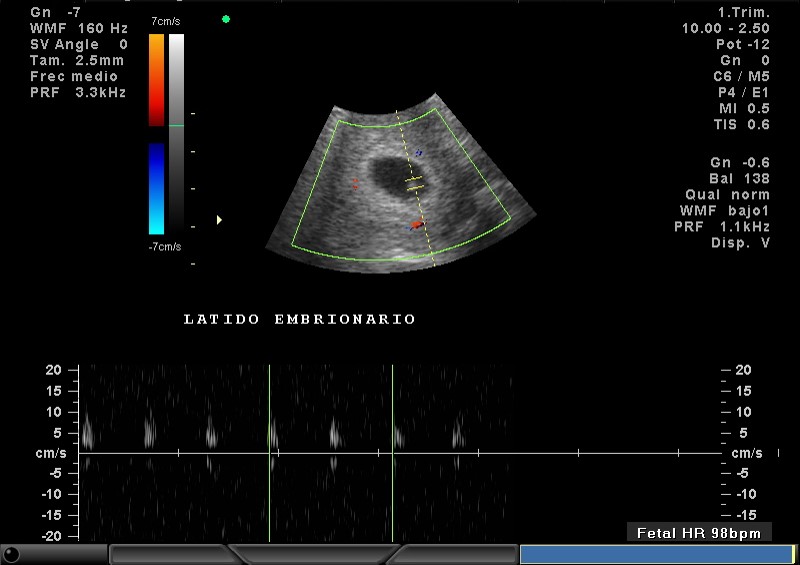

2D Y COLOR, VIVO, LATIDO CARDÍACO EMBRIONARIO

2D Y COLOR LATIDO CARDIACO EMBRIONARIO

2D Y COLOR, FRECUENCIA CARDIACA EMBRIONARIA